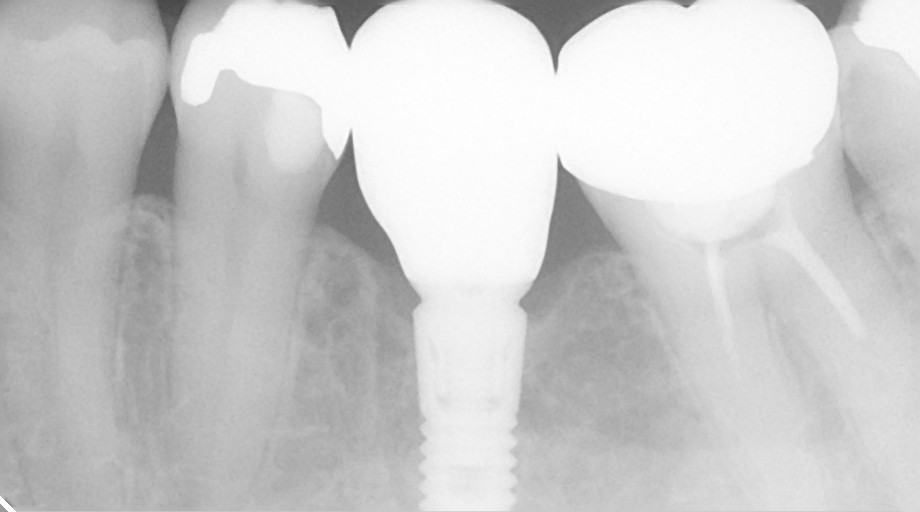

インプラント治療の症例紹介⑧

Before

After

主訴

歯の欠損の治療

治療内容

歯の欠損部の後方に既にインプラントが埋入されていたケース。欠損部にインプラントを埋入し上部構造で連結しました。

治療費

1,317,800 円(税込)

治療期間

11ヶ月

通院回数

15回

想定されたリスク

※経年的な歯肉退縮の恐れ.インプラント周囲炎の恐れがありました。

濱 仁隆先生

浜歯科

既存のインプラントと追加埋入を行ったインプラントを連結し完成させた症例です。